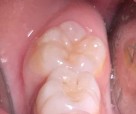

Bệnh nhân: Trần Gia K. 8 tuổi, nam, mã BA 8233/17

Sau ba tháng. ICDAS:2; Di: 21 | Sau sáu tháng. ICDAS:1; Di: 17 | Sau 18 tháng. ICDAS:0; Di: 05 |